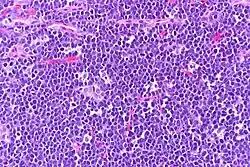

The tumor consists of sheets of a monotonous (i.e., similar in size and morphology) population of medium-sized lymphoid cells with high proliferative and apoptotic activity. The "starry sky" appearance seen[22] under low power is due to scattered tingible body-laden macrophages (macrophages containing dead apoptotic tumor cells). The old descriptive term of "small non-cleaved cell" is misleading. The tumor cells are mostly medium in size (i.e., tumor nuclei size similar to that of histiocytes or endothelial cells). "Small non-cleaved cells" are compared to "large non-cleaved cells" of normal germinal center lymphocytes. Tumor cells possess small amounts of basophilic cytoplasm with three to four small nucleoli. The cellular outline usually appears squared off.